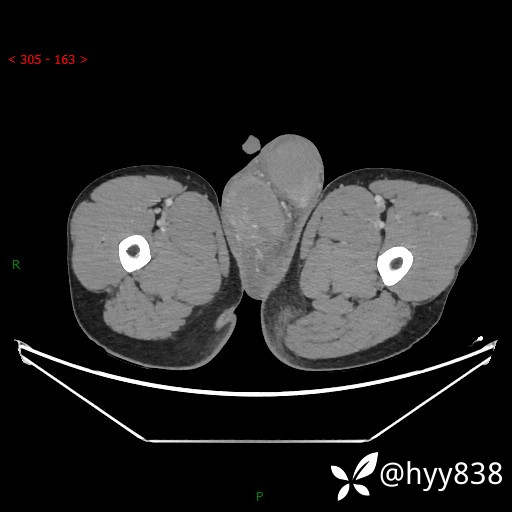

简要病史:,患者1周前无明显诱因开始出现双侧阴囊肿大、疼痛(右侧为甚),患者无发热畏寒,无腰痛、尿频、尿急、尿痛及肉眼血尿等症状,于外院就诊治疗后效果不佳,现患者为进一步治疗来我院,门诊以“双侧急性附睾炎”收入我科。 起病以来,患者精神、饮食、睡眠可,大小便正常,体力体重无明显改变。

临床诊断:附睾炎

讨论:病变性质?